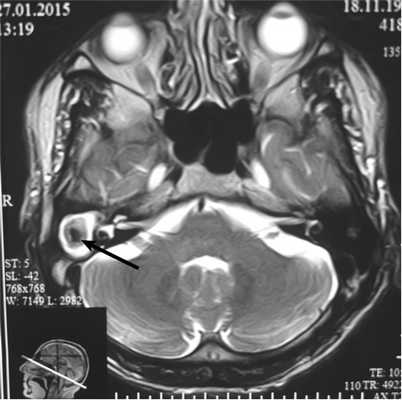

По данным МРТ головного мозга, в проекции пирамиды височной кости справа определяется окруженное капсулой объемное образование неоднородного сигнала с гипоинтенсивным центром размером до 21×21×20 мм (рис. 2).

Рис. 2. Больной М. МРТ головного мозга. Визуализируется мягкотканное новообразование в проекции пирамиды височной кости справа, неоднородное по структуре, с плотной капсулой и гипоинтенсивным центром (стрелка).